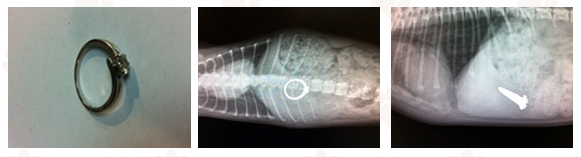

בצילום הרנטגן הראשון שבוצע על צד הגוף נראה בבירור אובייקט לא ביולוגי גדול מדי , יחסית לגודל הכלבה כמובן.

הצילום השני אישר את החשדות:

טבעת האירוסין שנעלמה לפני 5 ימים נמצאה!!

לאחר הרדמה קצרה יצאה הטבעת לאור העולם והוחזרה לאחר כבוד לבעליה.